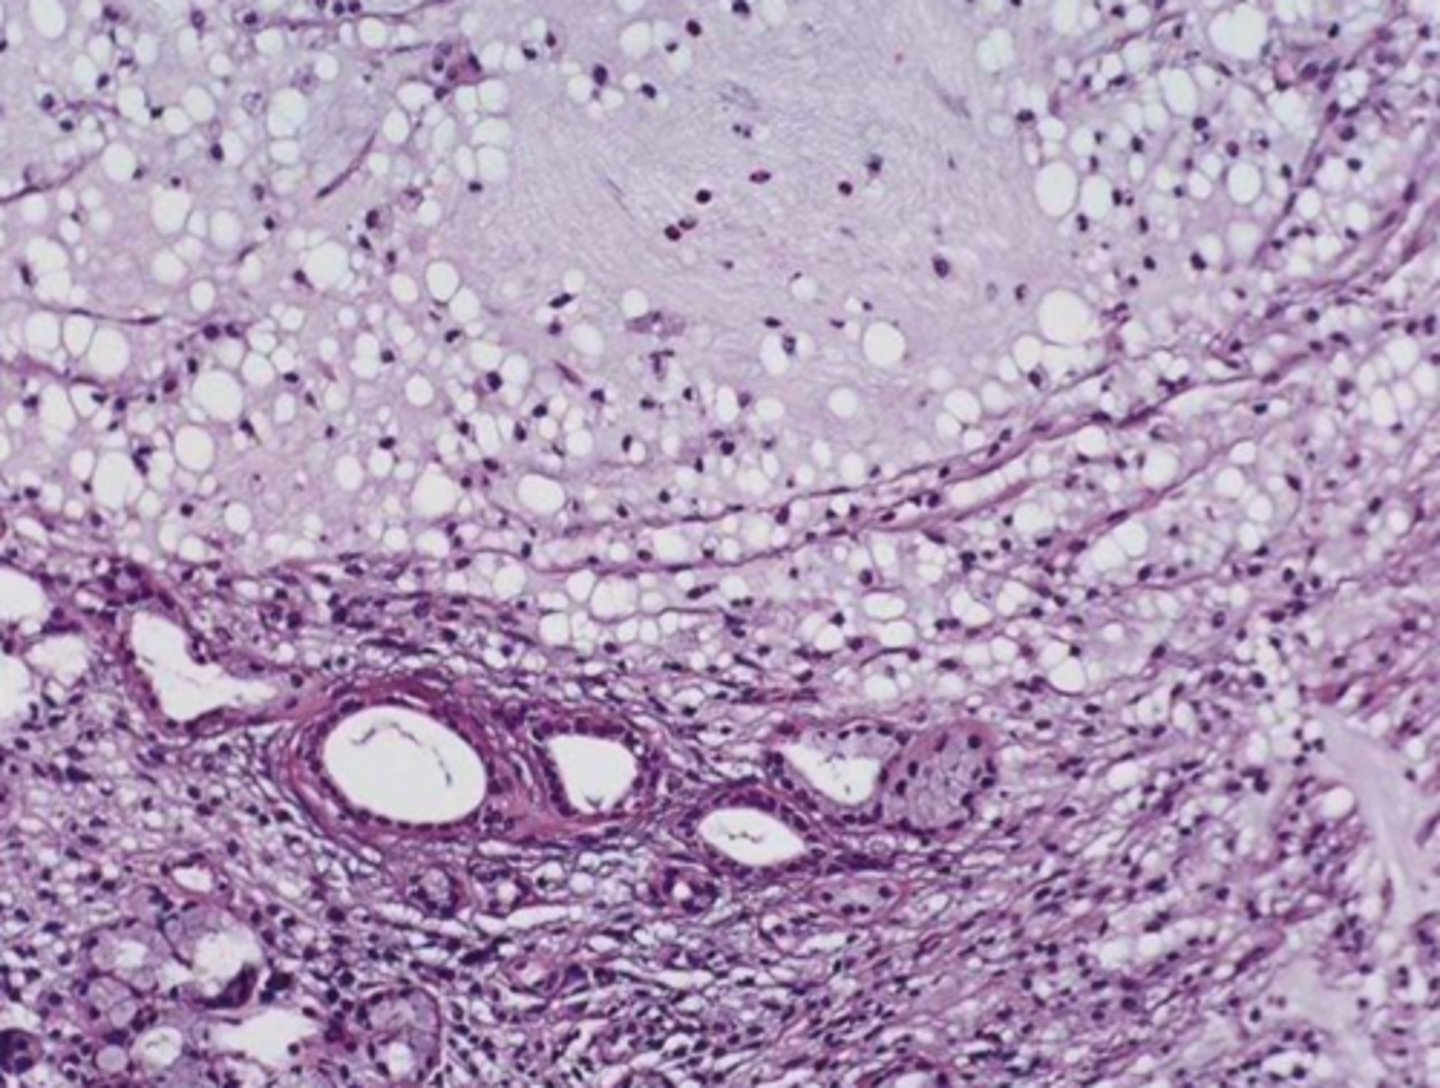

Sialolith

Calcified mass, Surrounded by inflamed and fibrotic salivary glands

Normal Parotid Parenchyma

Acinic Cell Carcinoma